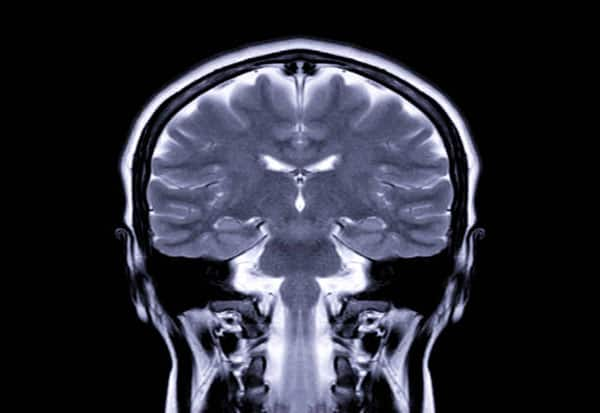

Effective ways to boost brain health!

Maintaining a sharp mind is crucial for brain health as we age. Engaging in mentally stimulating activities and regular physical exercise enhances memory, concentration, and cognitive function. Physical activity improves blood flow to the brain, reducing stress and anxiety.

Daily mental and physical exercises, even briefly, can aid in preventing neurodegenerative conditions. Embrace lifelong learning and explore new interests to keep your brain active.